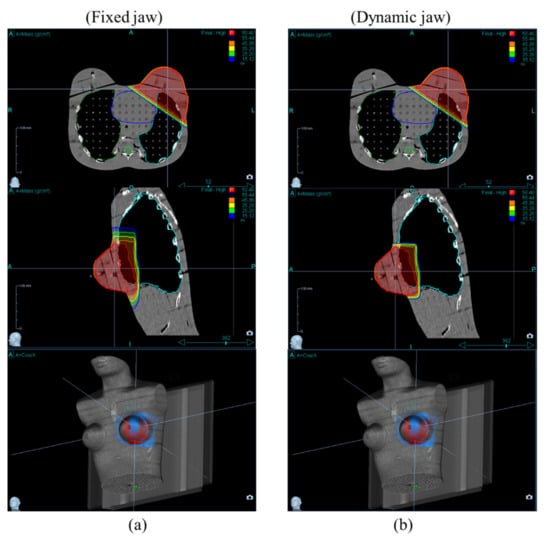

2.2. Treatment Planning

3. Results and Discussion

3.2. OARs Dose